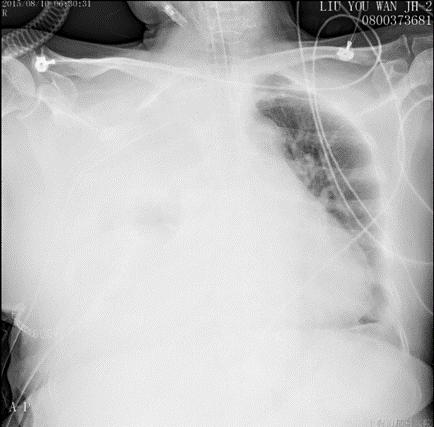

描述:溶栓2d后,胸引量:150ml

描述:溶栓3d后,胸引量:100ml

溶栓18h后,胸引量明显增多,同时提醒胸腔内大量血肿,因此于术后第五日,予以全麻下行VATS剖胸止血术,手术时间1.5h,术中失血600ml,输血球2单位,术后带气管插管入ICU。止血术后第一日胸引量450ml,复查血气正常,予以拔除气管插管,SPO2 96%,HR 81bpm,BP 135/88mmHg。

出院时情况:CTPA未见充盈缺损,下肢静脉彩超提示无血栓。血常规、凝血功能、肝、肾功能等无变化,患者一般情况可予以出院。